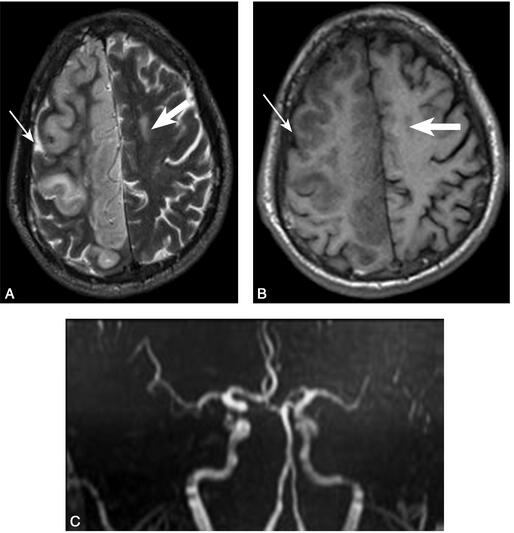

1小时条评论1 病例简介 例1,中年女性,因头晕、言语不清14日于2009年5月1日入院。患者14日前突然出现头晕,自觉言语不清,恶心,未呕吐,饮水偶有呛咳,全身乏力,肢体活动基本同前,在当地卫生室应用丹参、苦碟子注射液静脉点滴治疗14日,病情无缓解,以脑梗死收入院。既往...

1小时条评论1 病例简介 患者女,40岁,因发作性视物成双2年、言语不利8个月,眩晕伴视物变形20天于2010年1月30日入院。2年前于妊娠期无明确诱因地反复突发性视物成双,每次症状持续约2~3分钟后自行缓解,症状反复发作约10次,发作时肢体活动正常。8个月前,患者于行走时突发...